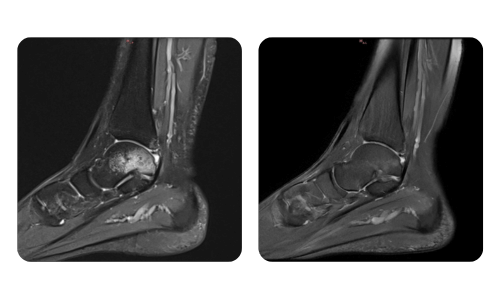

Betegeink előrehaladása, amelyet a hiperbár terápia előtt és után mértünk, tükrözi a kezelés hatékonyságát és pozitív hatását. Fedezze fel a Hyperbarium Oradea hiperbár terápiájának dokumentált eredményeit, amelyek klinikai értékeléseken és objektív adatokon alapulnak, és jelentős javulásokat mutatnak különböző állapotokban.